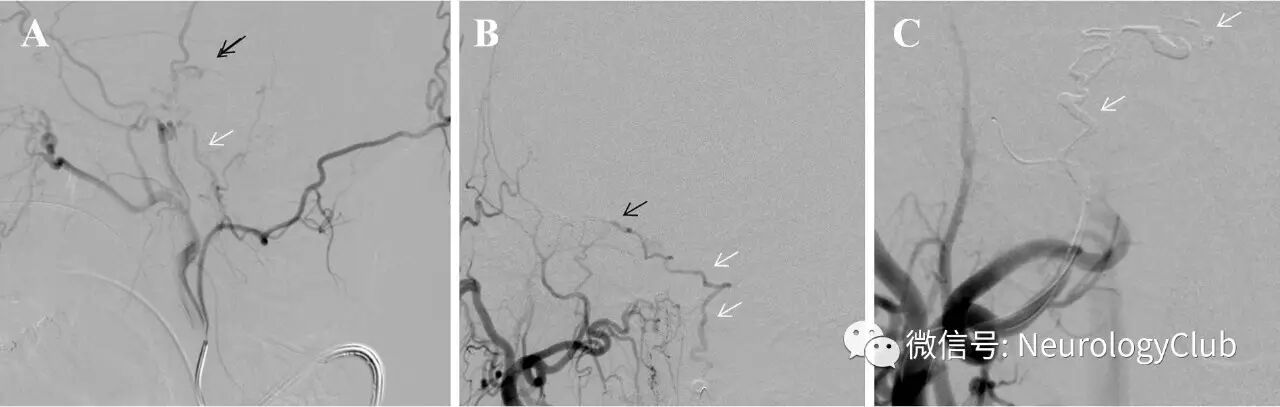

多次MRI提示脑干广泛弥漫的T2/FLAIR高信号,特别是脑桥和延髓。可见病灶边缘弥散受限,增强后未见明显强化。

图1为最近的MRI,此时患者脑干功能进一步恶化,已近乎完全性四肢瘫痪。

(图1:矢状位[A]和横断面[B]T2WI以及T1增强可见脑干病灶[箭])